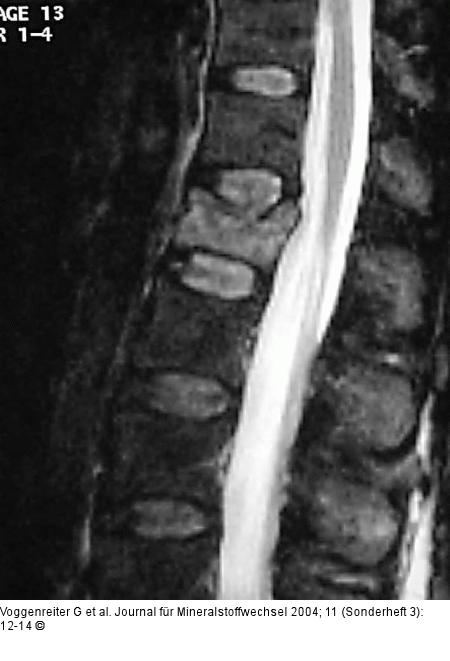

Abbildung 2a-c: LWK1-Fraktur 67jährige Patienten mit einer 4 Wochen alten LWK1-Fraktur und ausgeprägter Schmerzsymptomatik. In der TIRM-Sequenz des MRT erkennt man eine deutliche Signalanhebung in LWK1. |

Abbildung 2a-c: LWK1-Fraktur

67jährige Patienten mit einer 4 Wochen alten LWK1-Fraktur und ausgeprägter Schmerzsymptomatik. In der TIRM-Sequenz des MRT erkennt man eine deutliche Signalanhebung in LWK1. |